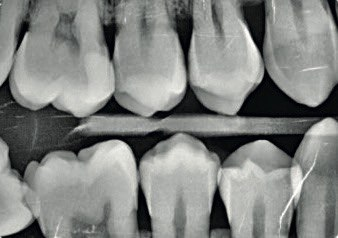

4. What surface require restoration?